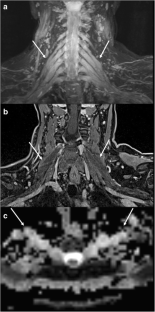

Fig. 4